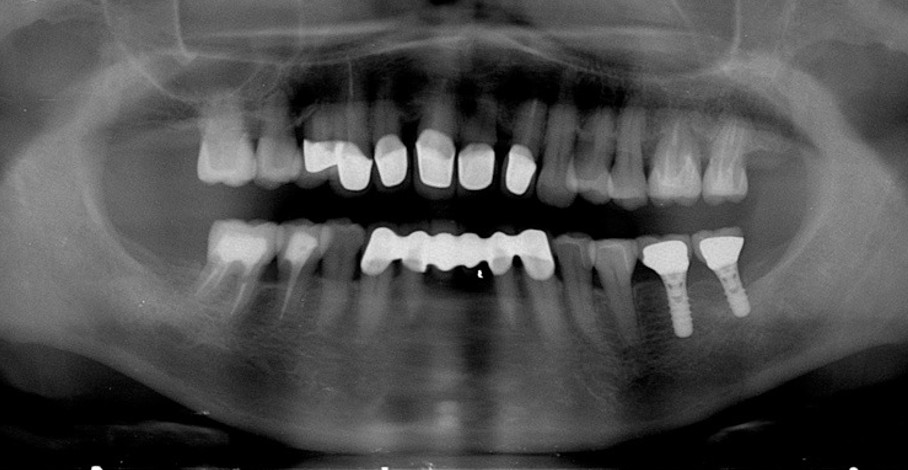

| 主訴 | 50代女性 以前いれた入れ歯が合わなくて使っていないので、しっかり噛めるようになりたい |

| 治療内容 | 矯正治療、インプラント治療、セラミック治療、金属床(部分入れ歯)を行いました。 |

| 治療費 | 4,200,000円(税込み) |

| 治療期間 | 2年(矯正治療期間 1年) |

| 治療回数 | 50回 |

| 想定されたリスク | 重度の歯周病で臼歯部の歯槽骨がかなり吸収していたため、インプラントが脱落するリスクがありました。 |